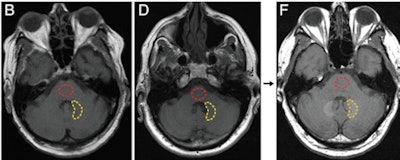

In the study, a research team led by neuroradiology fellow Dr. Robert McDonald, PhD, from the Mayo Clinic in Rochester, MN, examined tissue samples from the brains of 13 deceased patients who had received gadolinium-based contrast agents (GBCAs). They compared this group with 10 other deceased individuals who had not received contrast.

The researchers found concentrations of gadolinium in the dentate nuclei, pons, globus pallidus, and thalamus of the 13 patients who had received GBCAs. In fact, the deposits were present even in patients who received as few as four doses of gadolinium contrast.